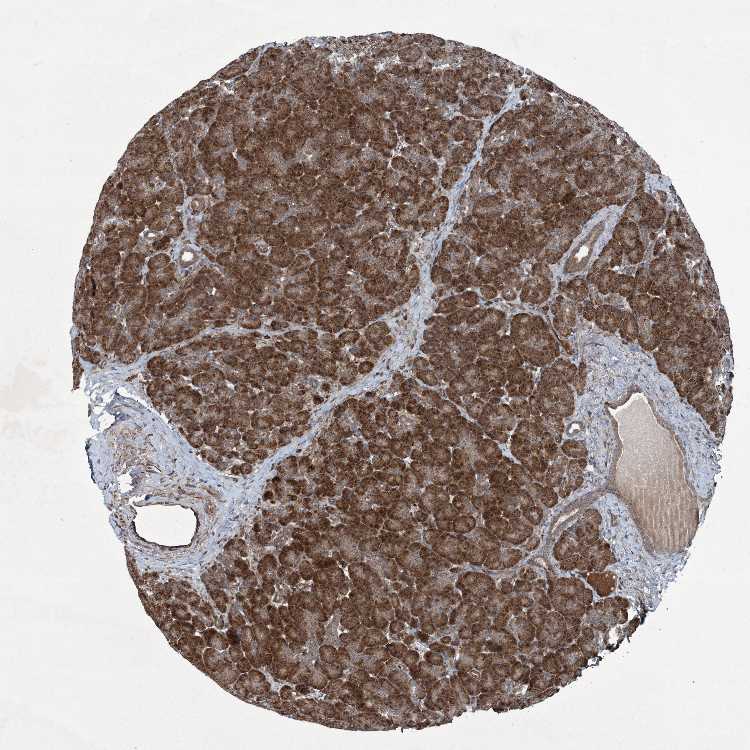

TISSUE PRIMARY DATA PANCREAS Show tissue menu

PANCREAS - Antibody stainingi

Antibody staining in the annotated cell types in the current human tissue is reported as not detected, low, medium, or high, based on conventional immunohistochemistry profiling in selected tissues. This score is based on the combination of the staining intensity and fraction of stained cells.

Each image is clickable and will lead to virtual microscopy that enables deeper exploration of all samples and also displays staining intensity scores, fraction scores and subcellular localization as well as patient and tissue information for each sample.

Antibody HPA035933

Exocrine glandular cells High